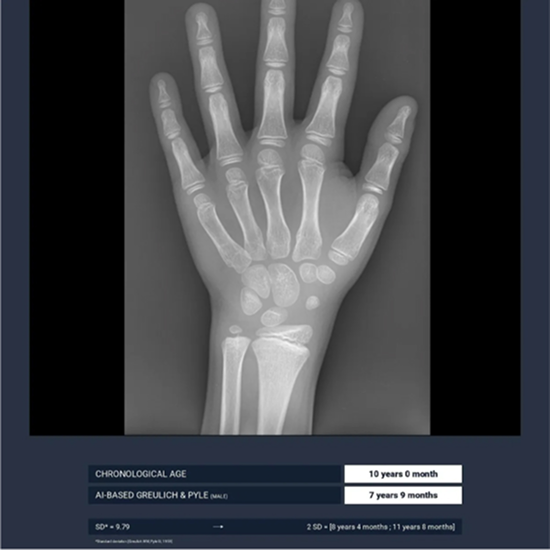

BoneAge: Revolutionizing Bone Age Assessment

BoneAge automates the assessment of bone age using the Greulich & Pyle atlas method, thereby saving valuable time while simultaneously ensuring precision.

Optimize the precision and consistency of your estimations

The AI-supported application BoneAge reduces both inter- and intra-variability.

Compared to the pediatric radiologist’s gold standard, the algorithm demonstrates utmost accuracy.

This is confirmed by Gleamers clinical study.